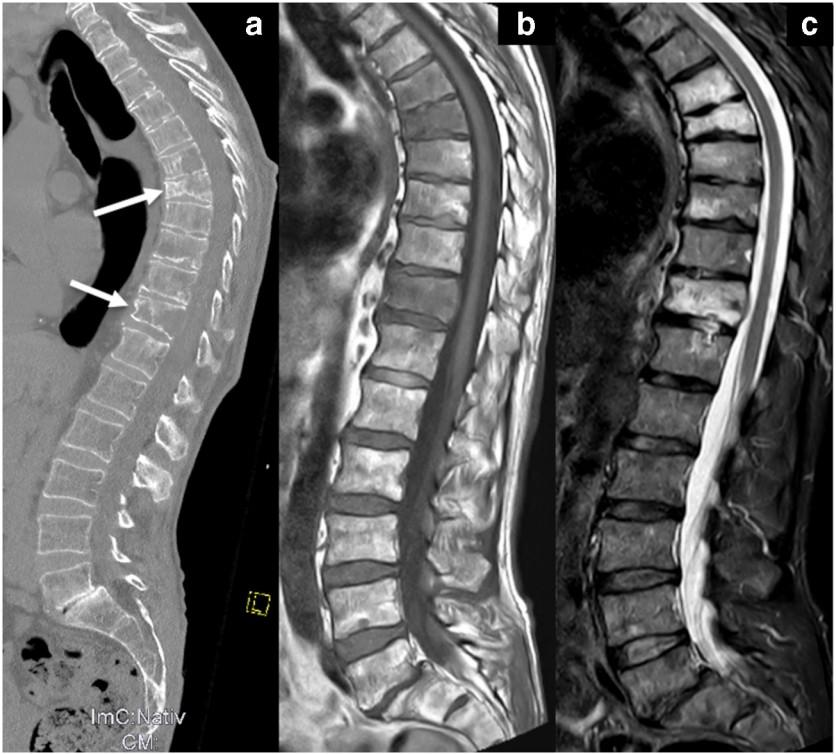

Bone Disease in Multiple Myeloma

Kyle RA. Mayo Clin Proc. 1975;50:29.

• A burdensome and frequent complication in MM

• Present in up to 80% of patients at diagnosis

• Characterized by osteolytic bone lesions secondary to increased bone resorption and impaired bone formation

• Sequelae

• Pathological fractures

• Osteoporosis

• Hypercalcemia

• Bone pain

• Spinal cord compression

Skeletal CT scan

K. Treiti et al. Skeletal Radiology 2021

MRI Scan